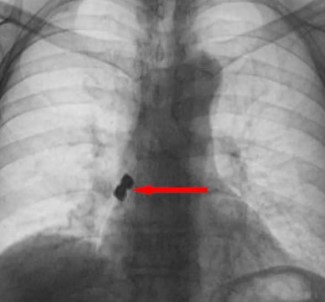

Olay Emirdag ilçesinde meydana geldi. Iddiaya göre, Belçika’nin Brüksel kentinde yasayan 56 yasindaki D.K., isimli gurbetçi vatandas implant dis tedavisi için Emirdag’daki bir klinige gitti. Operasyon esnasinda birbirine yapisik halde olan 2 adet implant bir anda hastanin disinden düstü. Implantlar ardindan hasta yutkununca akcigerlere kaçip sag nefes borusunu tikadi. Nefes almakta zorlanan D.K., ardindan Emirdag Devlet Hastanesi’ne kaldirildi. Burada yapilan müdahalenin ardindan D.K., Afyonkarahisar kent merkezindeki bir hastaneye sevk edildi. Burada D.K.’nin akcigerine kaçan implantlar cerrahi operasyona gerek kalmadan, bronkoskopi yöntemi adi verilen tibbi müdahale ile çikarildi. Implant yüzünden ölüm tehlikesi atlatan D.K., birkaç gün hastanede kaldiktan sonra taburcu edildi.